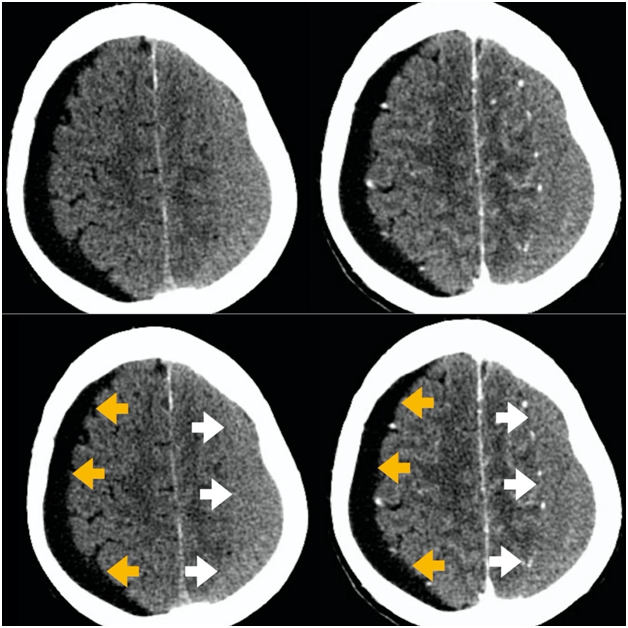

Figure 1 ACT scan without and with intravenous contrast - axial view. A bilateral subdural lesion was diagnosed. A hypodense subdural hygroma on the right side (orange arrows). On the left side,we can see an isodense chronic subdural hematoma (white arrows). Note the midline shift due to the chronic subdural hematoma mass effect.

Figure 2 CT scan without and with intravenous contrast, axial view. On the right side of the patient, we can see the spared cerebral sulci and no cortical veins inside the hygroma(orange arrows). On the left side, the sulci are compressed by the chronic subdural hematoma (white arrows).